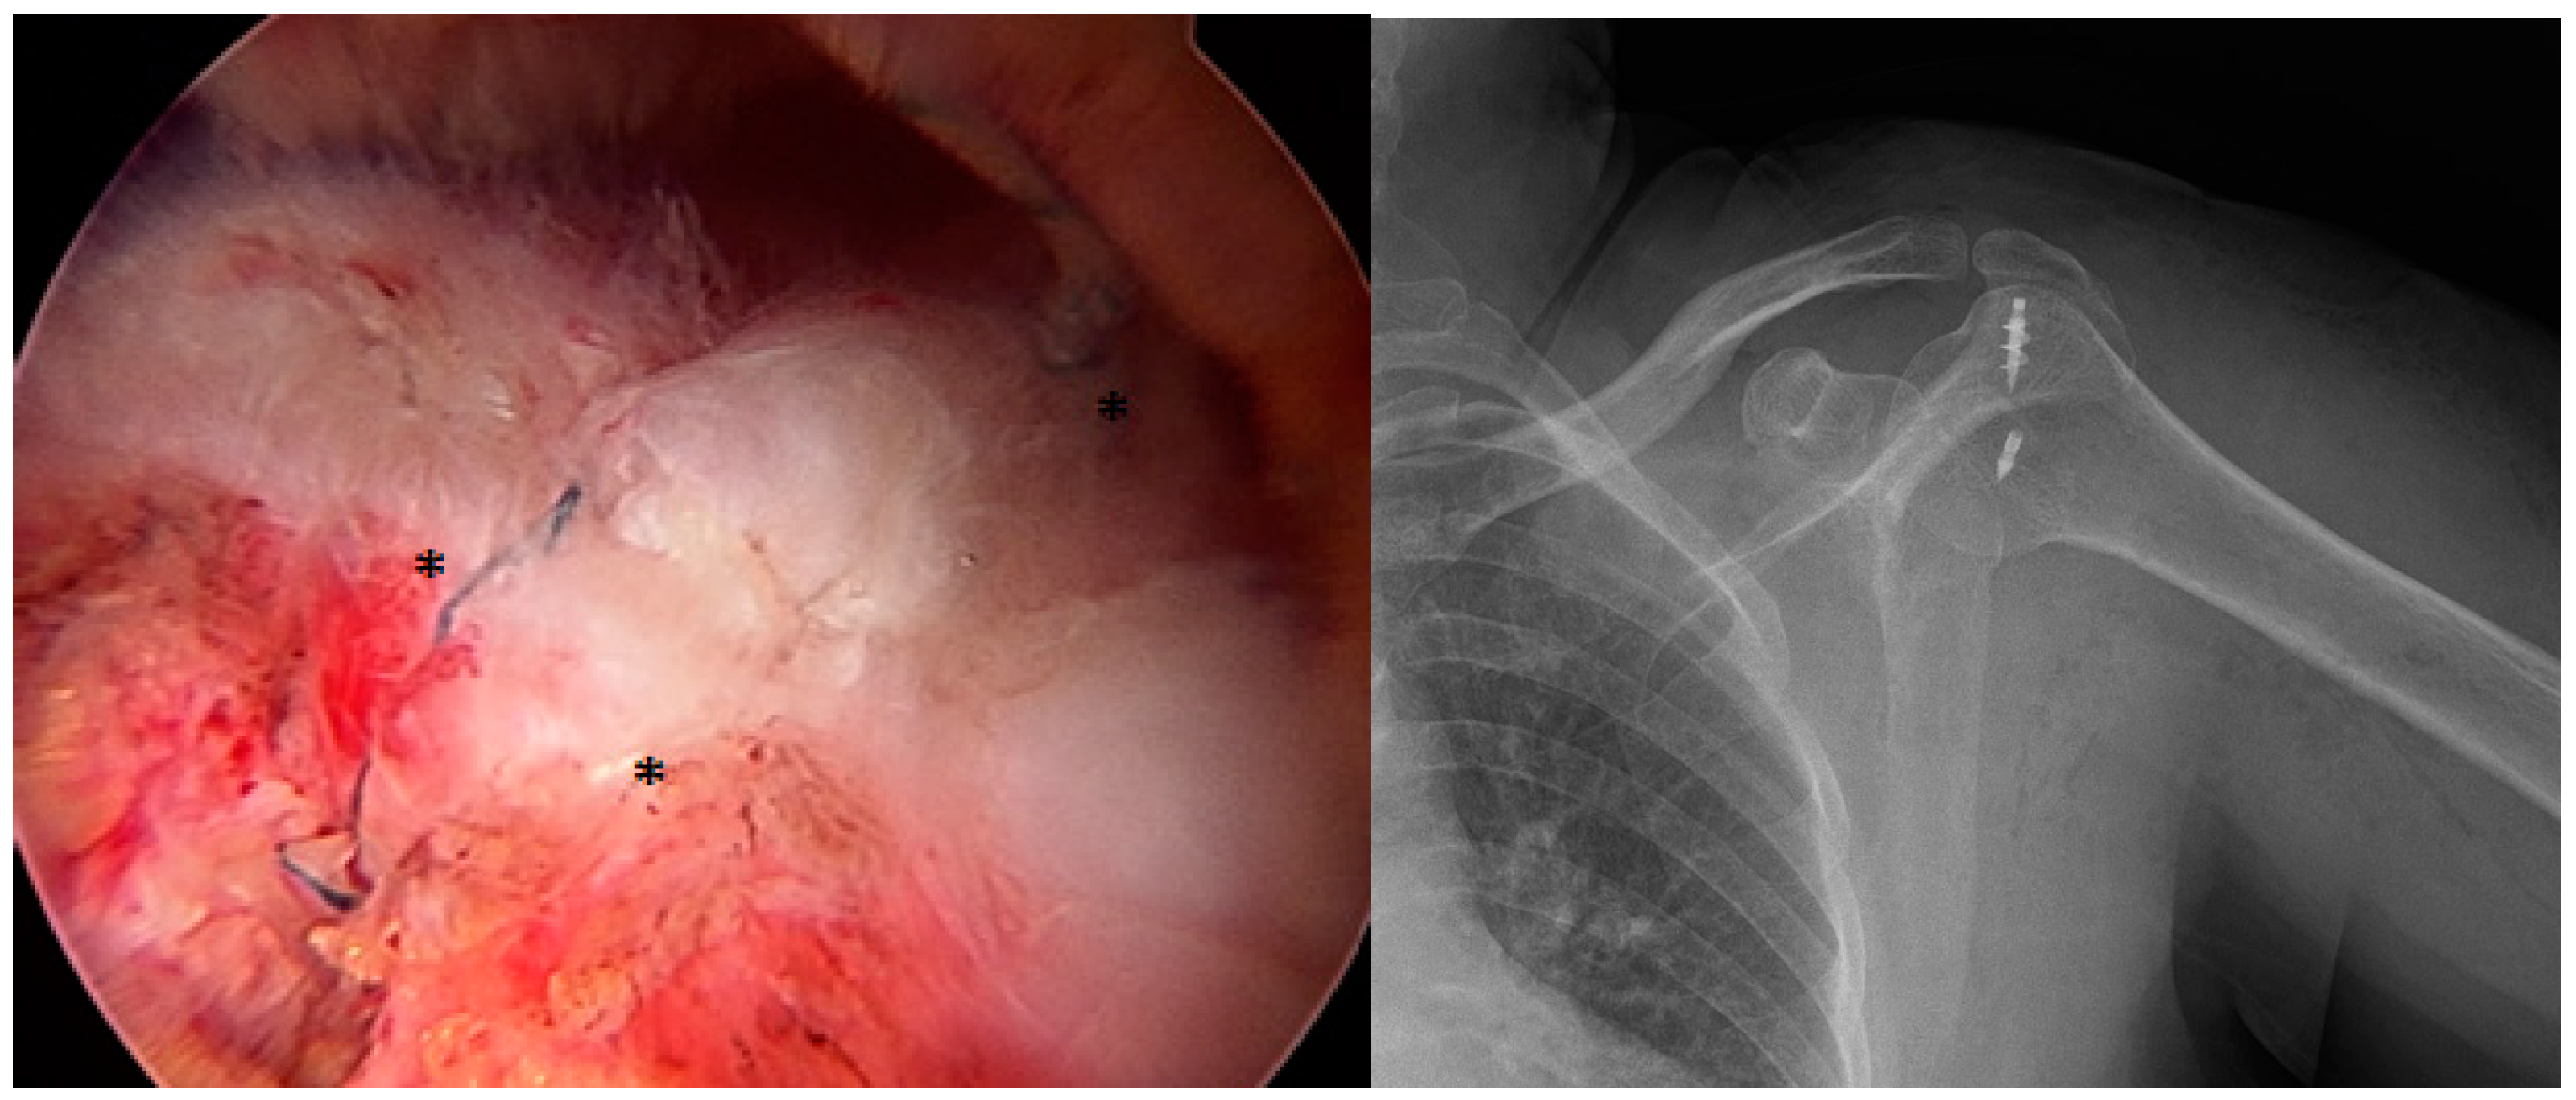

2.1. Surgical Procedure